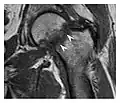

Figure 13: Partial osseous avulsion of the gluteal muscles at the greater trochanter in a 59-year-old man who presented with the right hip pain without a history of trauma. Lauenstein view and anteroposterior and radiographs (not shown) did not show an obvious fracture line or disruption of bony contours in the acetabulum or the right femoral neck. (a) Coronal T1-weighted MRI displays an incomplete fracture line extending partially from the greater trochanter (arrow). (b) Coronal short tau inversion recovery MRI shows heterogeneous hyperintensity in the same region (arrow) as well as hyperintensity within the gluteus medius and minimus muscles (arrowheads) consistent with tissue edema and hematoma.[1]